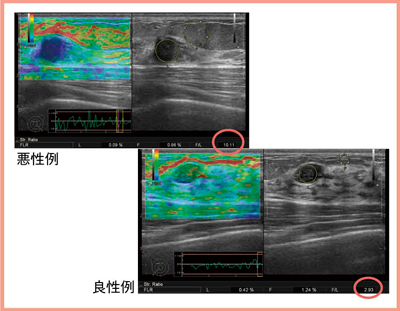

図2に悪性例と良性例を示す。エラストグラフィスコアでも判定はできるが,ROIを設定しFLRを算出すると,悪性例では10.11,良性例では2.93となり,より客観的に評価することができる。

図2 悪性例と良性例のFLR